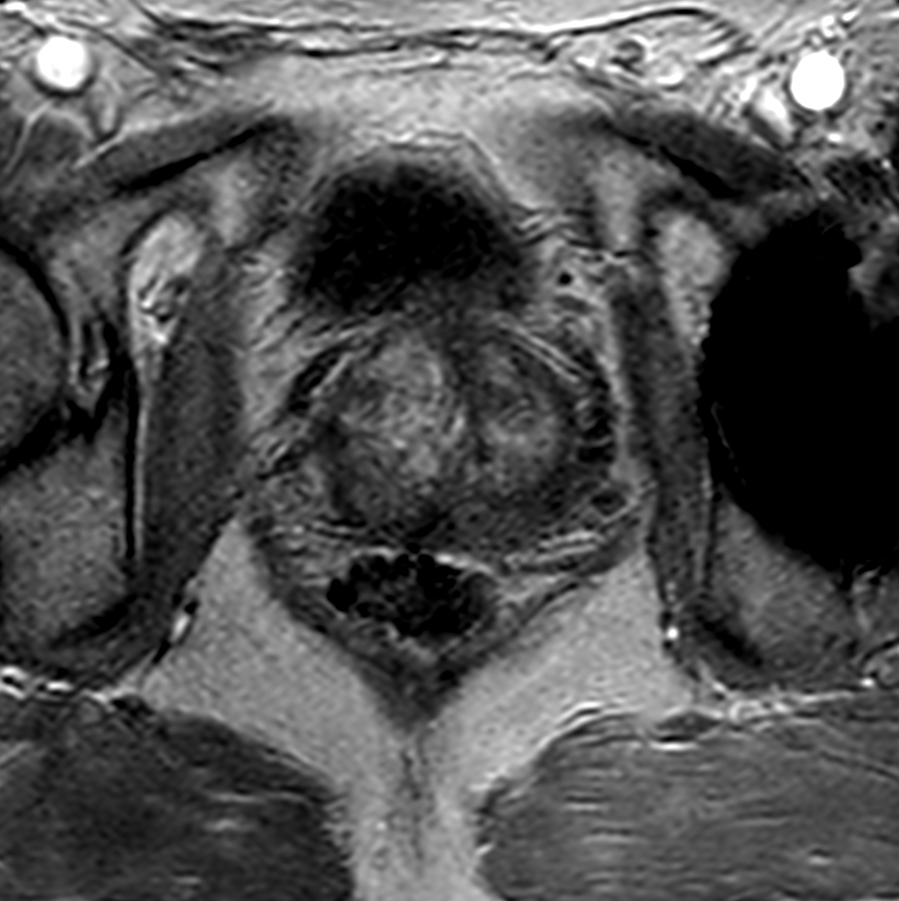

Axial T2w TSE